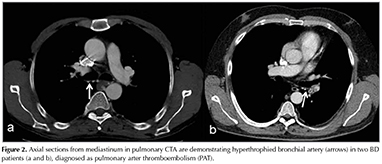

In our patient group, dilated or hypertrophied bronchial artery (larger than 1.5 mm) seen as serpiginous vessels around the hilum was common sign (8/12, 66.6%) in patients with PAI (Figure 2). This finding is defined in chronic thromboembolism as a response to a decrease in pulmonary flow and ischemia (19). It is a sign of a chronic compensatory process to pulmonary artery occlusion. We postulate that PA involvement in BD is not as acute as pulmonary thromboembolism, so there is enough time for bronchial artery to be hypertrophied. The existence of hypertrophied bronchial arteries was correlated with PA involvement and cardiac abnormal findings in this study. Therefore, we think that this finding is a valuable clue in constituting the diagnosis of PAI in patients with BD. The incidence of this finding was not discussed as much in the literature related to BD. In a previous article, the authors described a case of acute thrombosis in PA revealing hypertrophied bronchial arteries, despite immunosuppressive and anticoagulant treatment (18).